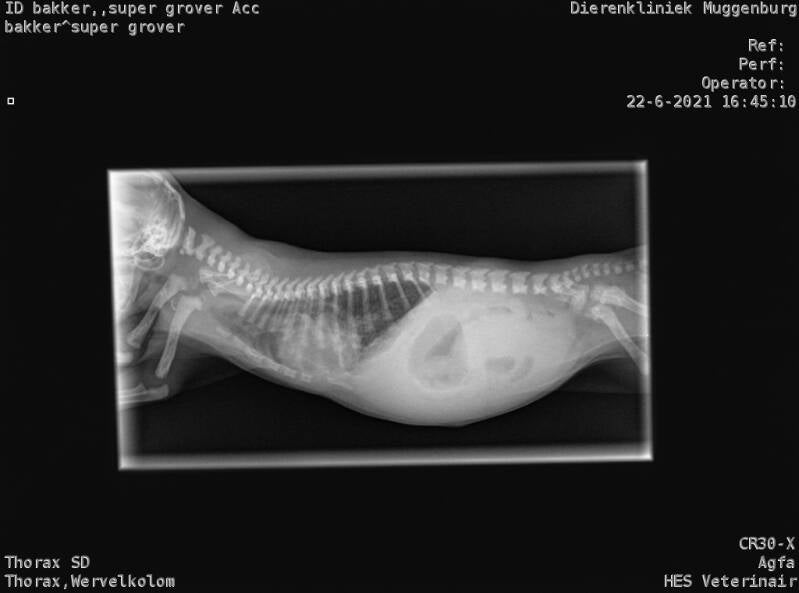

Omdat de medicatie niet goed genoeg aansloeg en Grover niet echt opknapte en benauwd had opnieuw bij de dierenarts geweest. Een fikse longontsteking werd bij hem geconstateerd. Hij heeft een injectie gehad met een paardenmiddel hopelijk zal hij genezen en wordt hem dit niet fataal

Helaas is Super Grover na een zware strijd in de avond overleden aan een zware longontsteking. We hebben hem de afgelopen dagen gevoed ondersteund dmv medicatie, ondanks de goede zorgen en hulp van onze dierenarts mocht het helaas niet zo zijn. We zijn erg verdrietig dag Grover er niet meer is. Loïs heeft rustig afscheid van hem kunnen nemen.